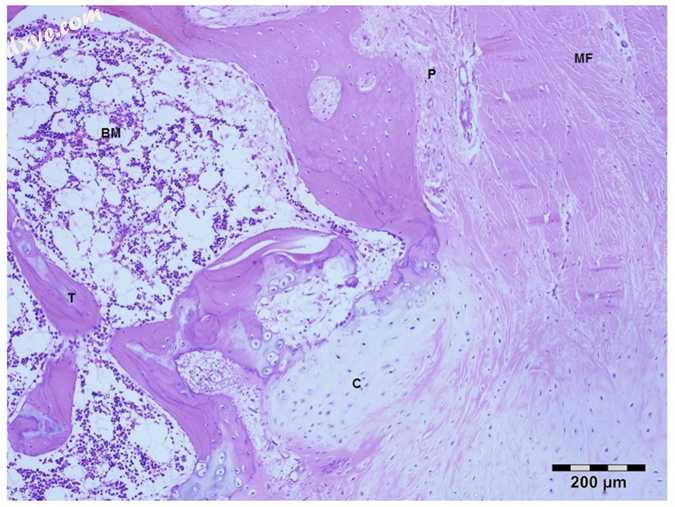

在骨移植组(n = 4)中,骨厚度显著减小。 与血管化骨瓣不同,骨板层系统未发育良好。 有骨管的Haversian系统数量减少,其中存在血管和神经纤维。 骨小梁与多个软骨小岛部分融合。 有相当大的骨腔,其中含有造血组织和小梁之间的疏松结缔组织。 此外,在BG组中,层流系统和Haversian管中的血管没有很好地发育,并且空隙中存活的骨细胞数量减少(图8)。

8.jpg

图8

BG组的脱钙部分。

P,骨膜; MF,肌纤维; C,软骨组织; T,小梁; BM,骨髓。 苏木精和伊红染色。Bar=200μm左右。